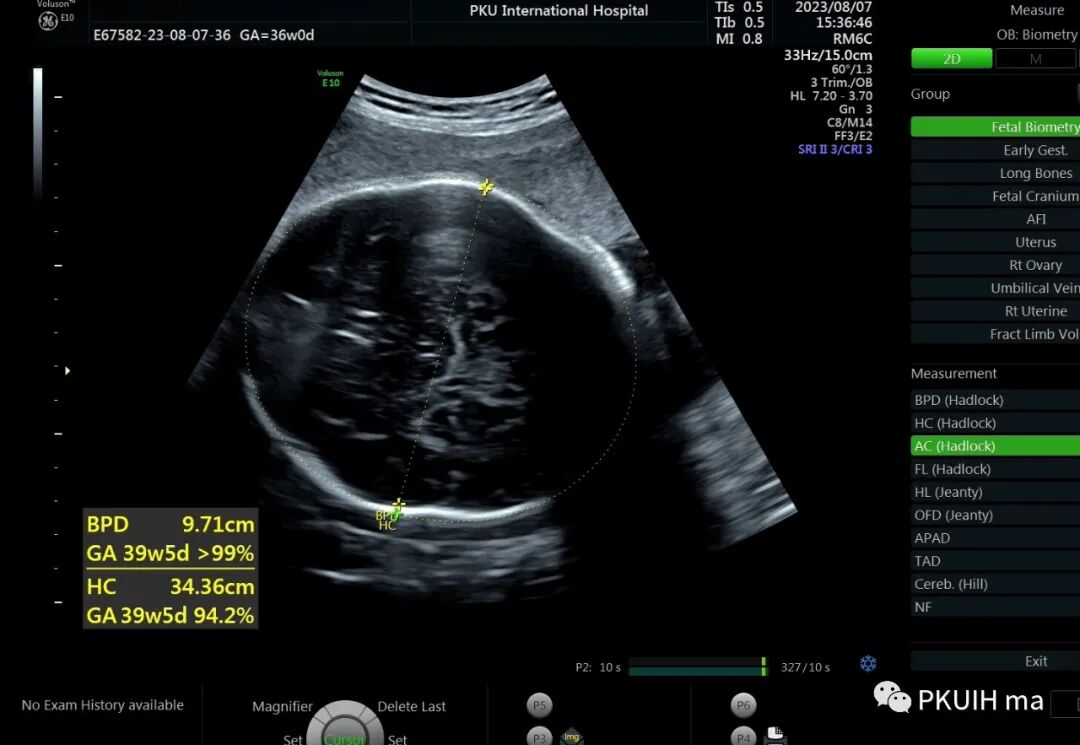

36周检查发现肢体越来越短,股骨和肱骨只相当于25-6周

头围双顶径已经大于相对孕周了,明显的头大肢体短。足底长度正常范围。